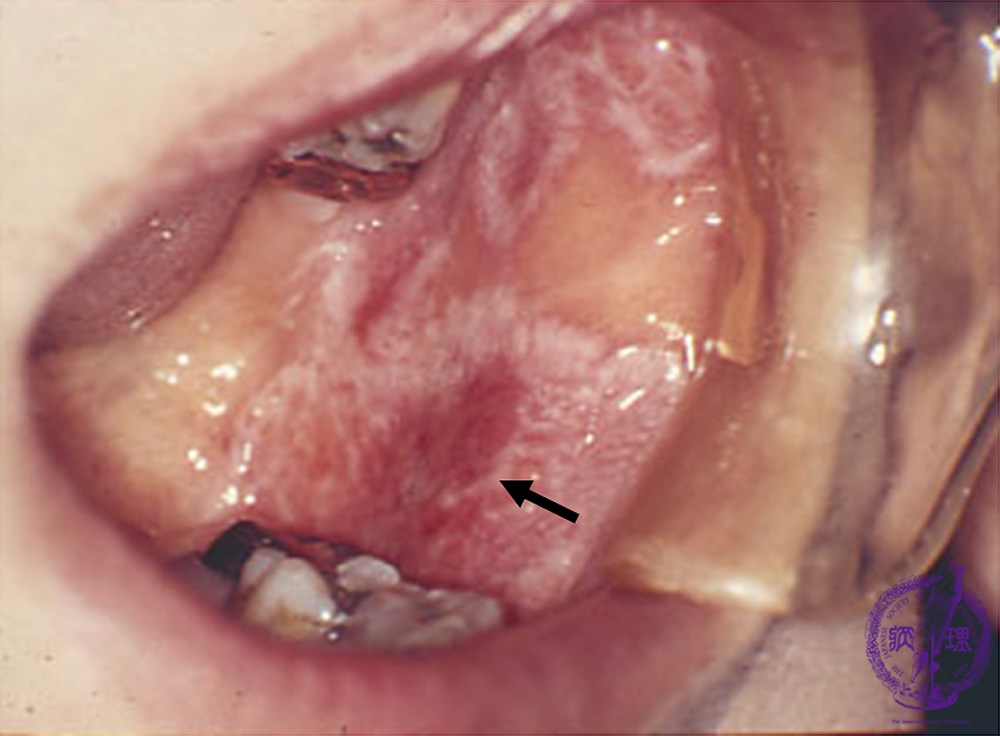

Macroscopic finding:Intraoral photograph. A white reticular (lace-like) lesion with erosive reddish area (arrow) in the buccal mucosa.

Click the image to see the enlarged image.